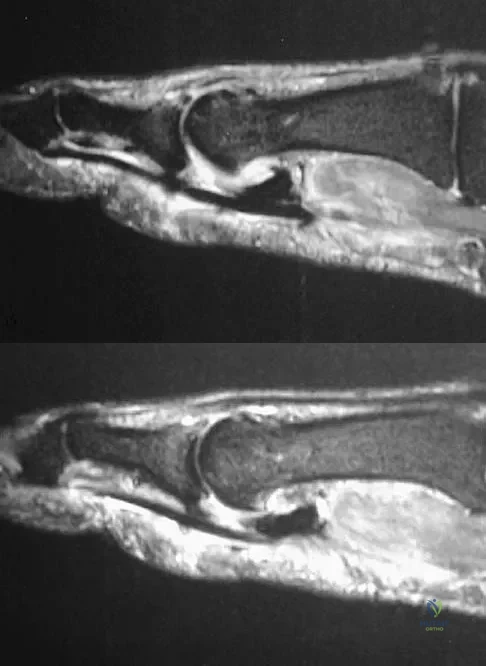

Question 52High Yield

A patient notes pain under the first metatarsophalangeal joint following a soccer injury. The MRI scans shown in Figures 27a and 27b reveal what pathologic finding?

Explanation